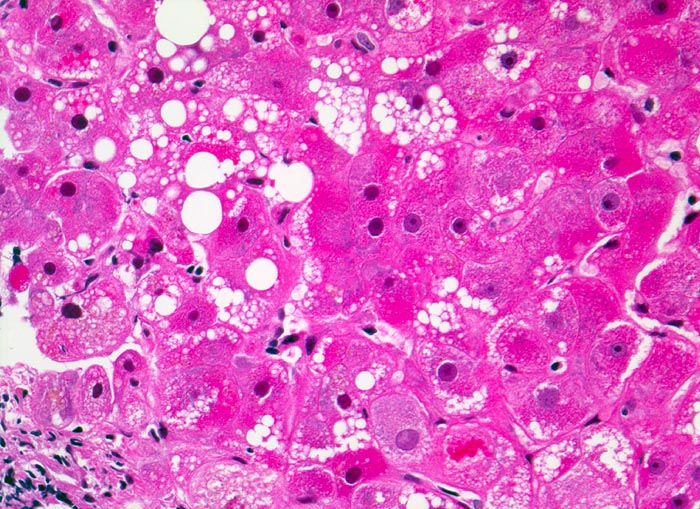

Cholestatische Mallory-Denk bodies

Ballonierte Hepatozyten mit feintropfiger Verfettung. Einzelne enthalten cholestatische Mallory-Denk bodies.

Adipositas permagna. Unklare Cholestase.

Histologie

320